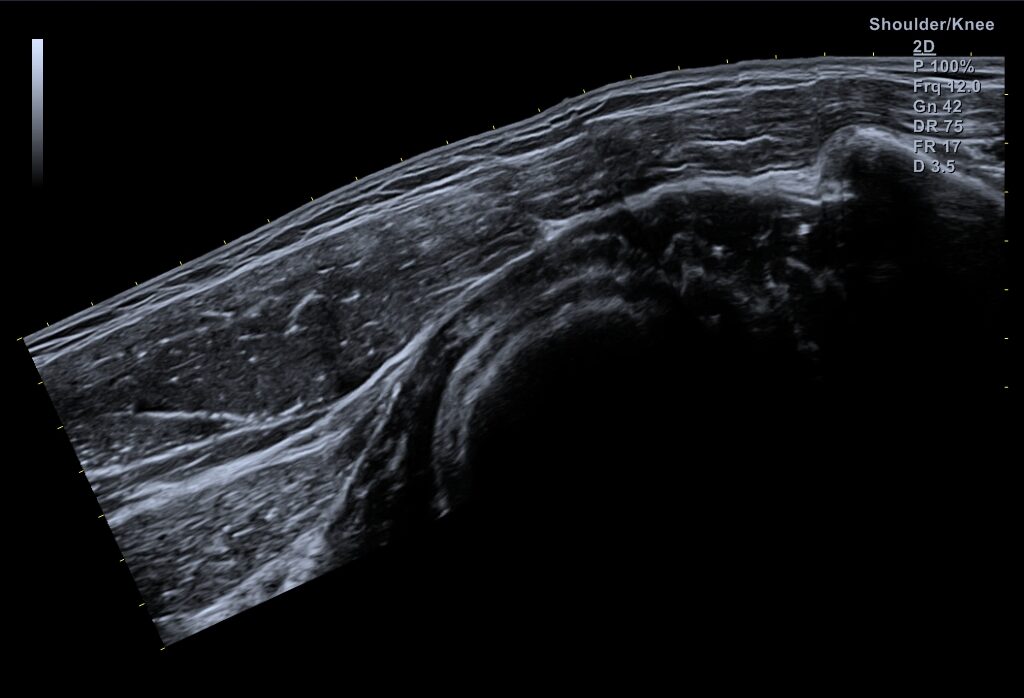

Ultrasonography-guided anterior approach for axillary nerve blockade: An anatomical study

Authors: González-Arnay E, Jiménez-Sánchez L, García-Simón D, Valdés-Vilches L, Salazar-Zamorano CH, … Read more about Ultrasonography-guided anterior approach for axillary nerve blockade: An anatomical study